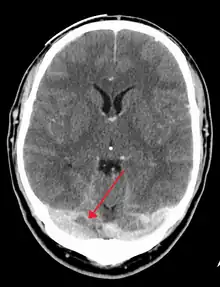

The diagnosis is usually by computed tomography (CT scan) or magnetic resonance imaging (MRI) to demonstrate obstruction of the venous sinuses.[3] After confirmation of the diagnosis, investigations may be performed to determine the underlying cause, especially if one is not readily apparent.

There are various neuroimaging investigations that may detect cerebral sinus thrombosis. Cerebral edema and venous infarction may be apparent on any modality, but for the detection of the thrombus itself, the most commonly used tests are computed tomography (CT) and magnetic resonance imaging (MRI), both using various types of radiocontrast to perform a venogram and visualise the veins around the brain.[3]

Computed tomography, with radiocontrast in the venous phase (CT venography or CTV), has a detection rate that in some regards exceeds that of MRI. The test involves injection into a vein (usually in the arm) of a radioopaque substance, and time is allowed for the bloodstream to carry it to the cerebral veins – at which point the scan is performed. It has a sensitivity of 75–100% (it detects 75–100% of all clots present), and a specificity of 81–100% (it would be incorrectly positive in 0–19%). In the first two weeks, the "empty delta sign" may be observed (in later stages, this sign may disappear).[11] The empty delta sign is characterized by enhancement of the dural wall without intra-sinus enhancement.[6]